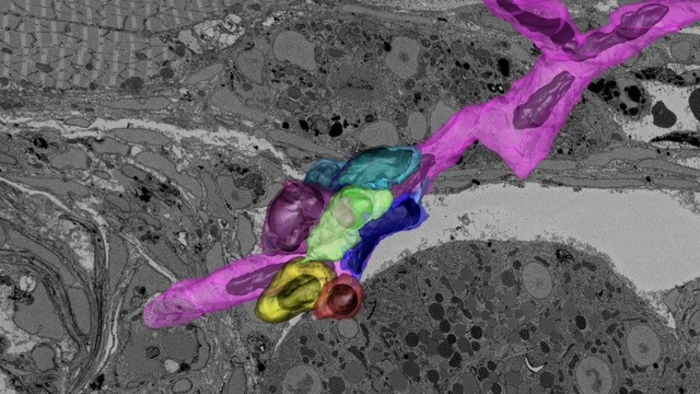

在一个大型的3D电子显微镜数据集中追踪特征,揭示了斑马鱼血液干细胞(绿色)及其周围的生态位支持细胞,这一组照片的方法将有助于研究人员了解促进血液干细胞健康的因素,这反过来可能有助于开发血液疾病和癌症的治疗方法。

图片来源:Keunyoung Kim